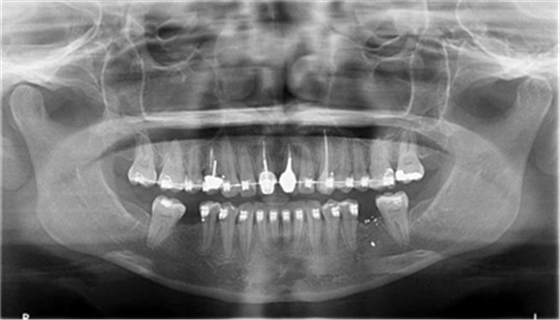

圖1a.病例1在正畸排齊后的臨床和放射學(xué)檢查。曲面斷層片顯示初期治療后良好的牙根排列,但下頜右側(cè)第二磨牙仍舊有些近中傾斜

一位29歲的女性患者,雙側(cè)下頜第一磨牙缺失,來院要求修復(fù)治療。缺失牙從未進(jìn)行修復(fù),導(dǎo)致牙槽嵴萎縮,第二磨牙近中傾斜,第三磨牙已拔除。其咬合關(guān)系為尖牙關(guān)系安氏II類錯畸形,作者團(tuán)隊決定通過正畸治療來糾正錯畸形和改進(jìn)咬合關(guān)系。因此,其治療計劃包括雙側(cè)下頜第二磨牙直立和種植體支持式修復(fù)體來替代缺失的第一磨牙。

為患者采用了直絲弓自鎖托槽(Damon,Ormco)。最開始用0.016×0.025 英寸的不銹鋼弓絲(Damon,Ormco)進(jìn)行矯正和排齊,歷時7 個月。在磨牙直立加力之前,下頜第一磨牙位點無牙區(qū)的近遠(yuǎn)中距離為右側(cè)6.5mm、左側(cè)9mm(圖1)。磨牙遠(yuǎn)移和直立的目標(biāo)是實現(xiàn)雙側(cè)最終冠修復(fù)體的近遠(yuǎn)中直徑達(dá)到10mm。右側(cè)第一磨牙位點的大小差異比左側(cè)更大,牙槽嵴吸收更多,頰舌徑約4.5mm(圖2)。在詳細(xì)解釋同期牙槽嵴增量和加速磨牙直立程序后,患者選擇右側(cè)位點進(jìn)行種植治療。因此,為了加速該位點的空間建立,圍繞第二磨牙行選擇性去皮質(zhì)術(shù)和同期牙槽嵴增量術(shù)。